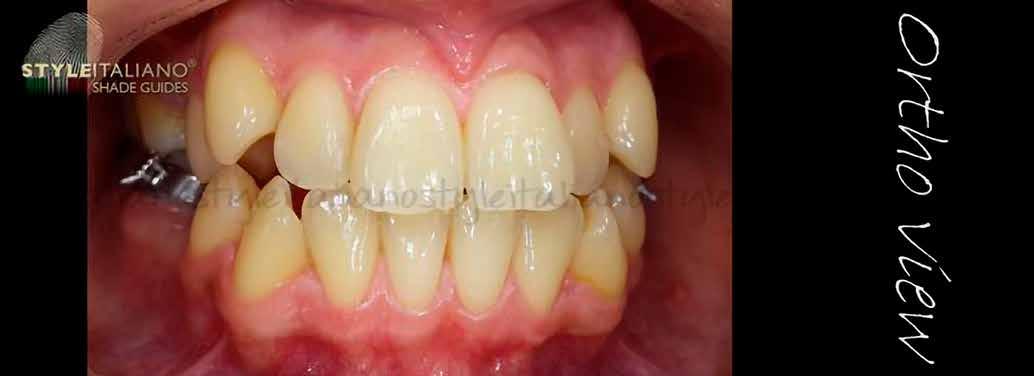

Egy 30 éves, negatív kórtörténettel rendelkező beteg azzal a kéréssel fordult hozzánk, hogy cseréljük ki az UR1 traumája után, 10 évvel korábban készült korábbi kompozit-helyreállítást.

A klinikai vizsgálat során az UR1 reagál a viabilitási tesztre, és az ugyanazon a napon készült röntgenfelvételen nem mutat periapikális elváltozásokat (1. ábra).

Az UR1 elszíneződött, és palatálisabb helyzetben van, mint az ellenoldali központi UL1 (2. ábra)

Az esztétikai elemzés a gingivális zenit aszimmetriáját mutatja az UR1 és az UL1 között. Parodontális szonda segítségével, plexusérzéstelenítés után, az IA

típusú funkcionális hám megváltozott passzív erupcióját igazoljuk Coslet és mtsai. osztályozása szerint (3. ábra)

A lehető legkonzervatívabb helyreállító kezelés elvégzése érdekében a páciensnél, figyelembe véve a megtartott fogelem korát és vitalitását, a tervezés és a diagnosztikai felviaszolás után a közvetlen kompozit-helyreállítás elvégzése mellett döntünk.

1. ábra: Röntgenfelvétel periapikális elváltozás nélkül. – 2. ábra: Az UR1 elszíneződése és palatális helyzete.